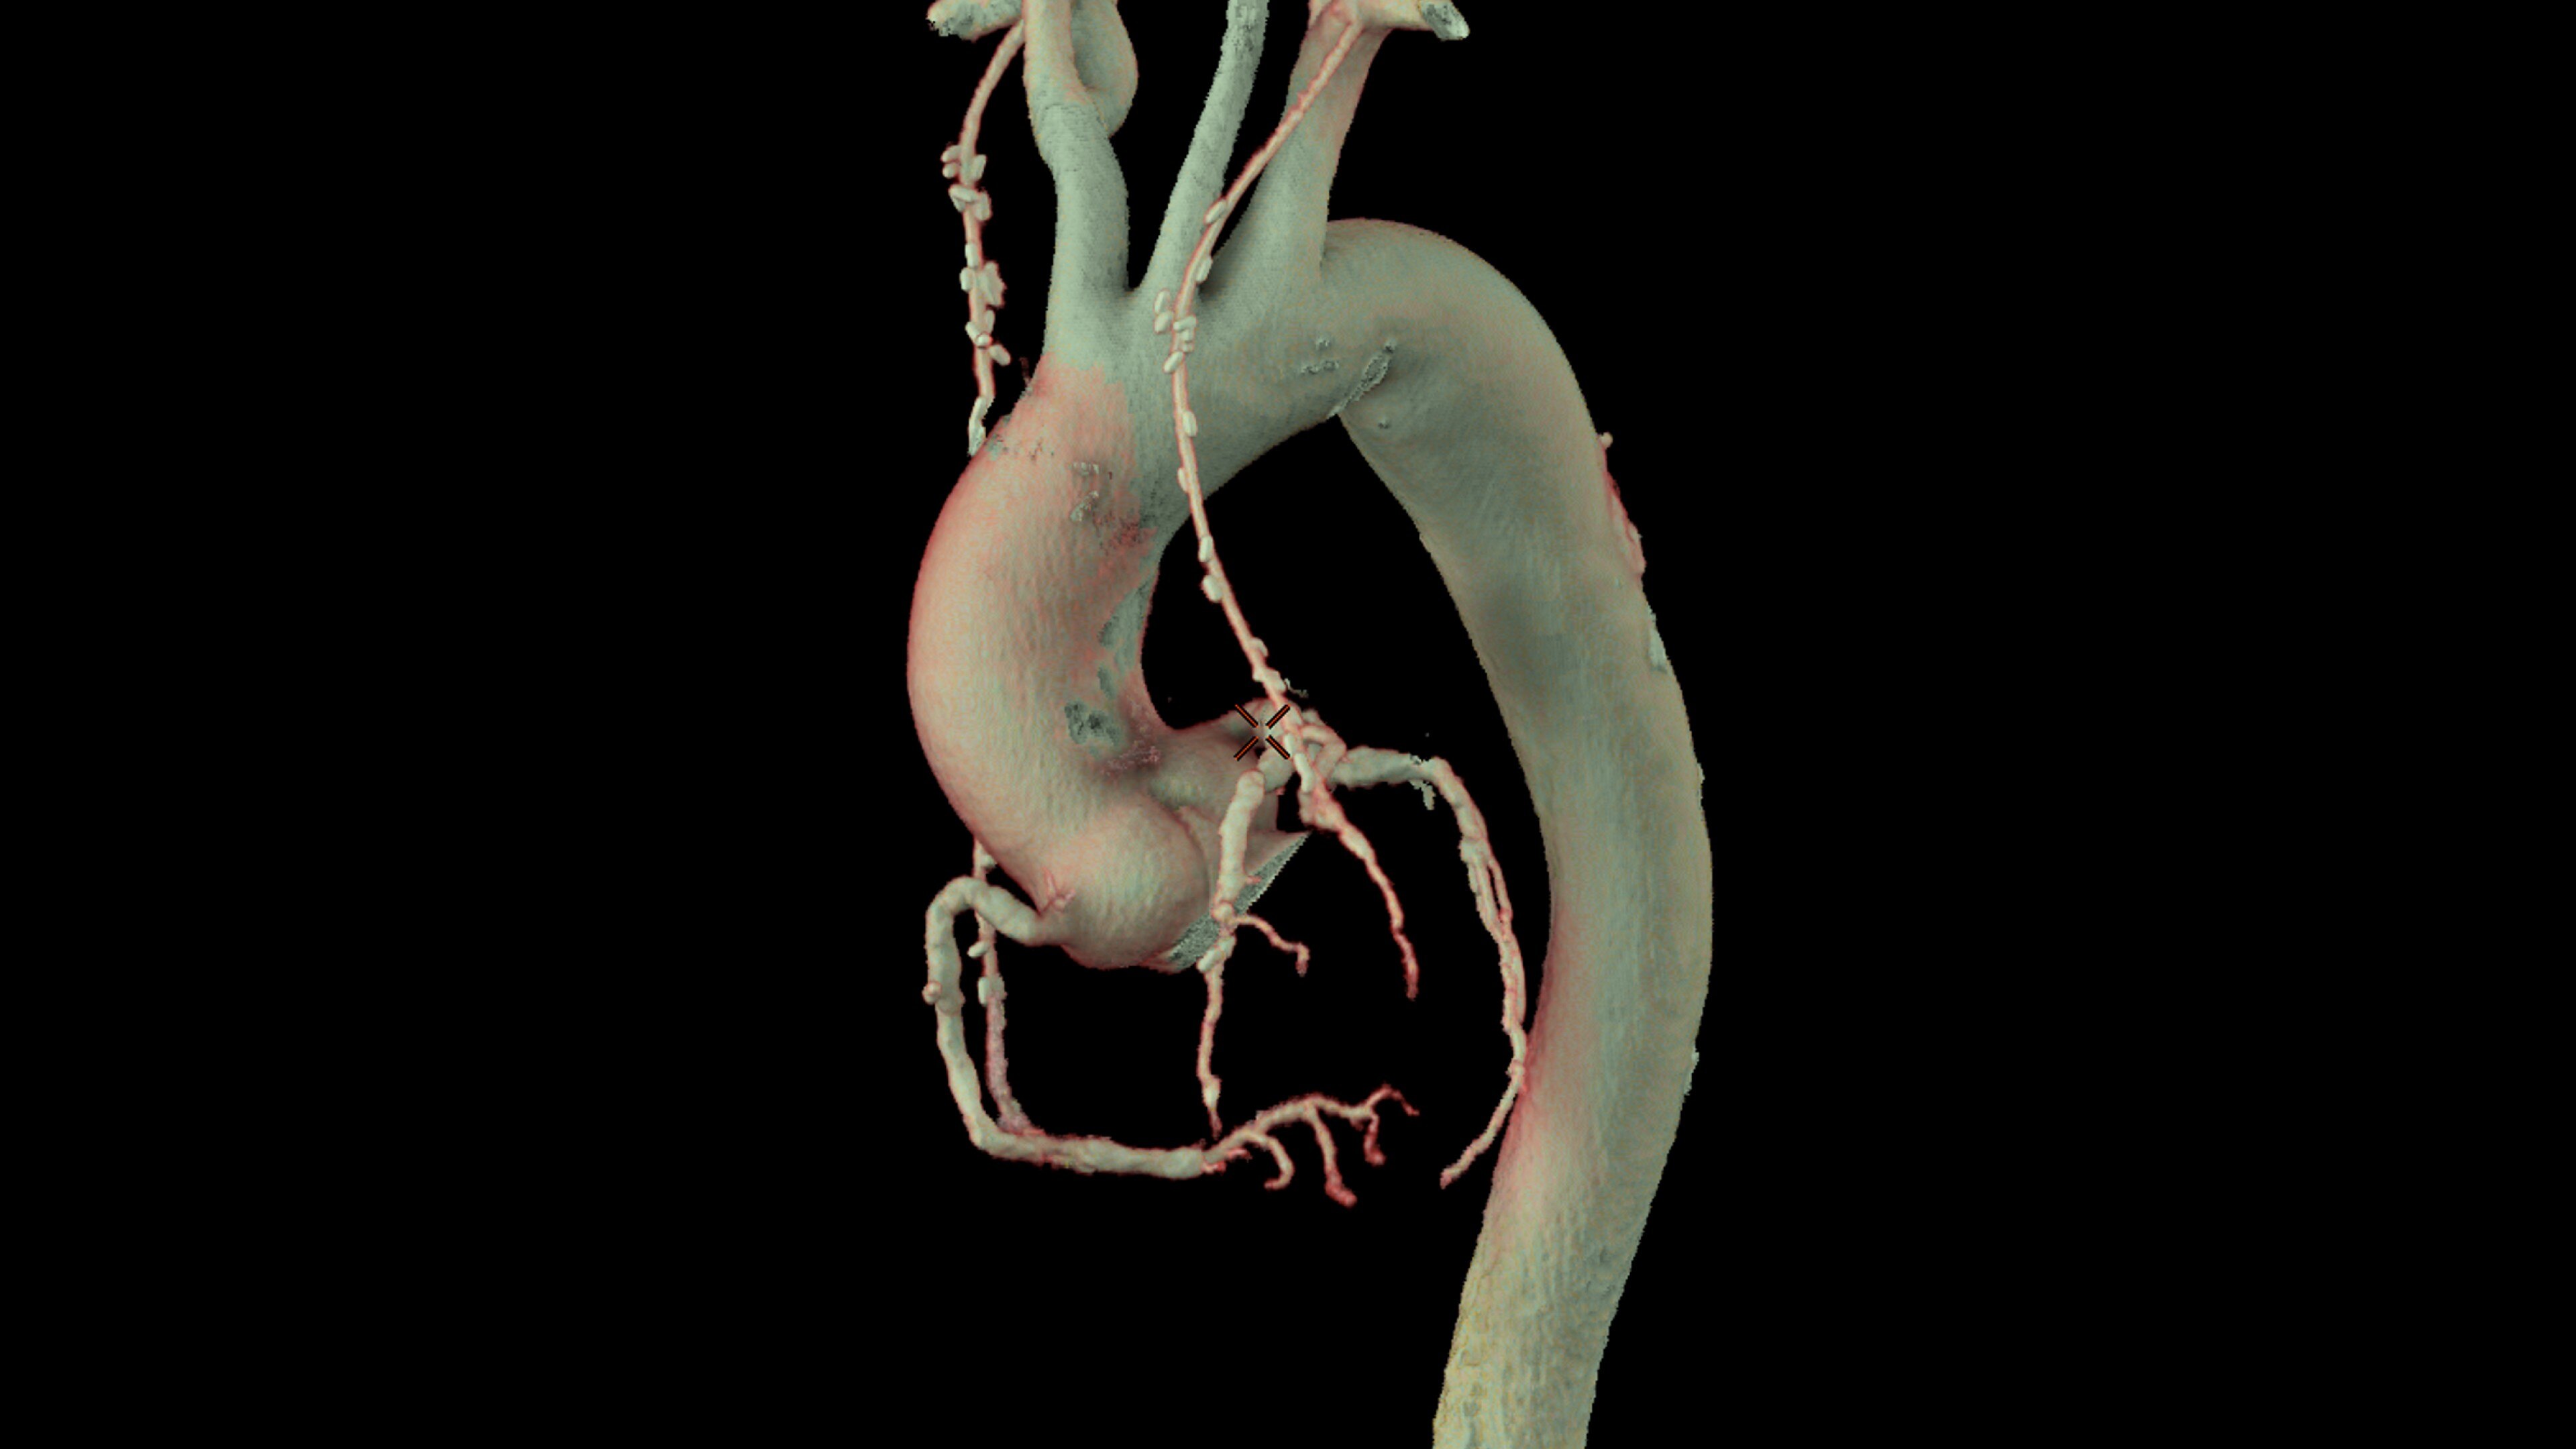

Automatically segments the coronary tree, tracks and labels the coronary arteries

• Pre-processing automatically recognizes cardiac datasets and performs all segmentations as data arrives on the system saving processing time

• Auto Coronary analysis automatically segments the coronary tree, tracks and labels the coronary arteries